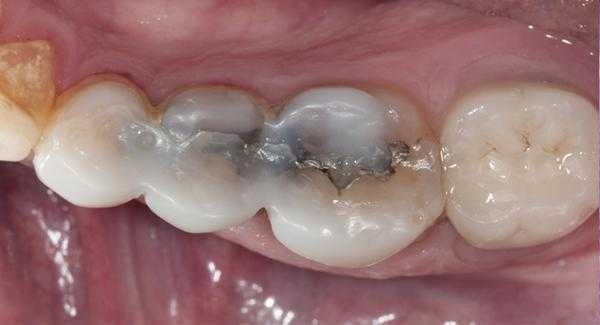

На рисунке 1 показана исходная ситуация.Классический фиссурный кариес зубов 16 и 17. Как и в большинстве подобных случаев, кариозный процесс протекает абсолютно бессимптомно.